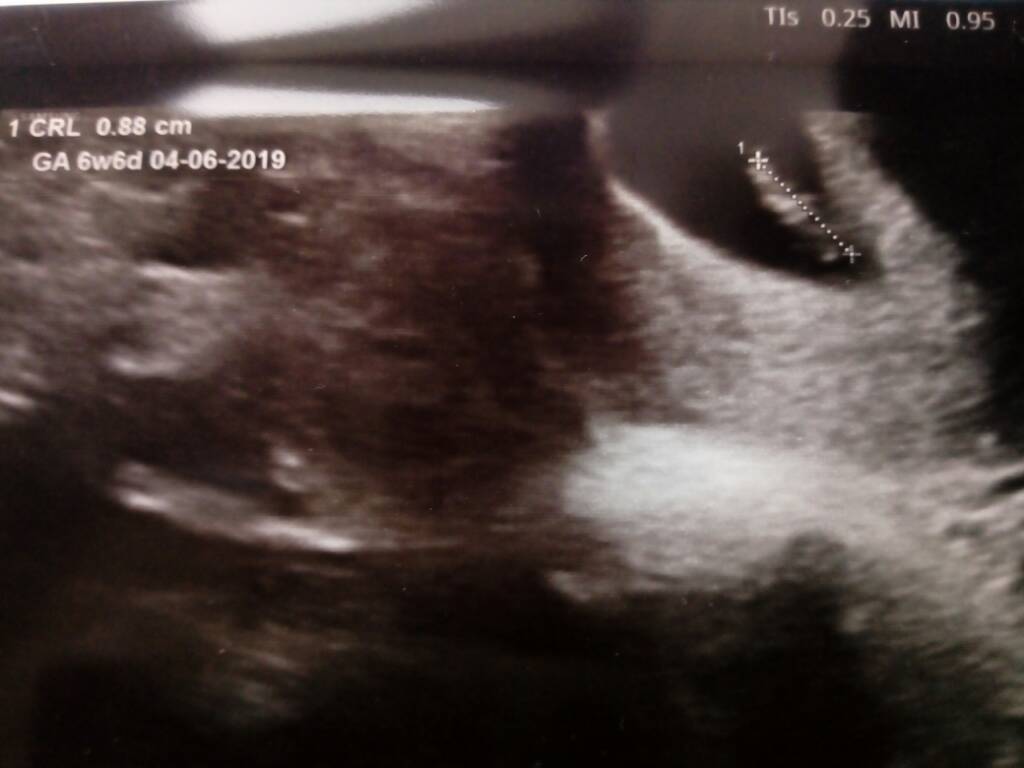

Cudo :*Tutaj też wrzucam pierwsze foto mojej fasolki [emoji7] [emoji7] [emoji7] Zobacz załącznik 905981